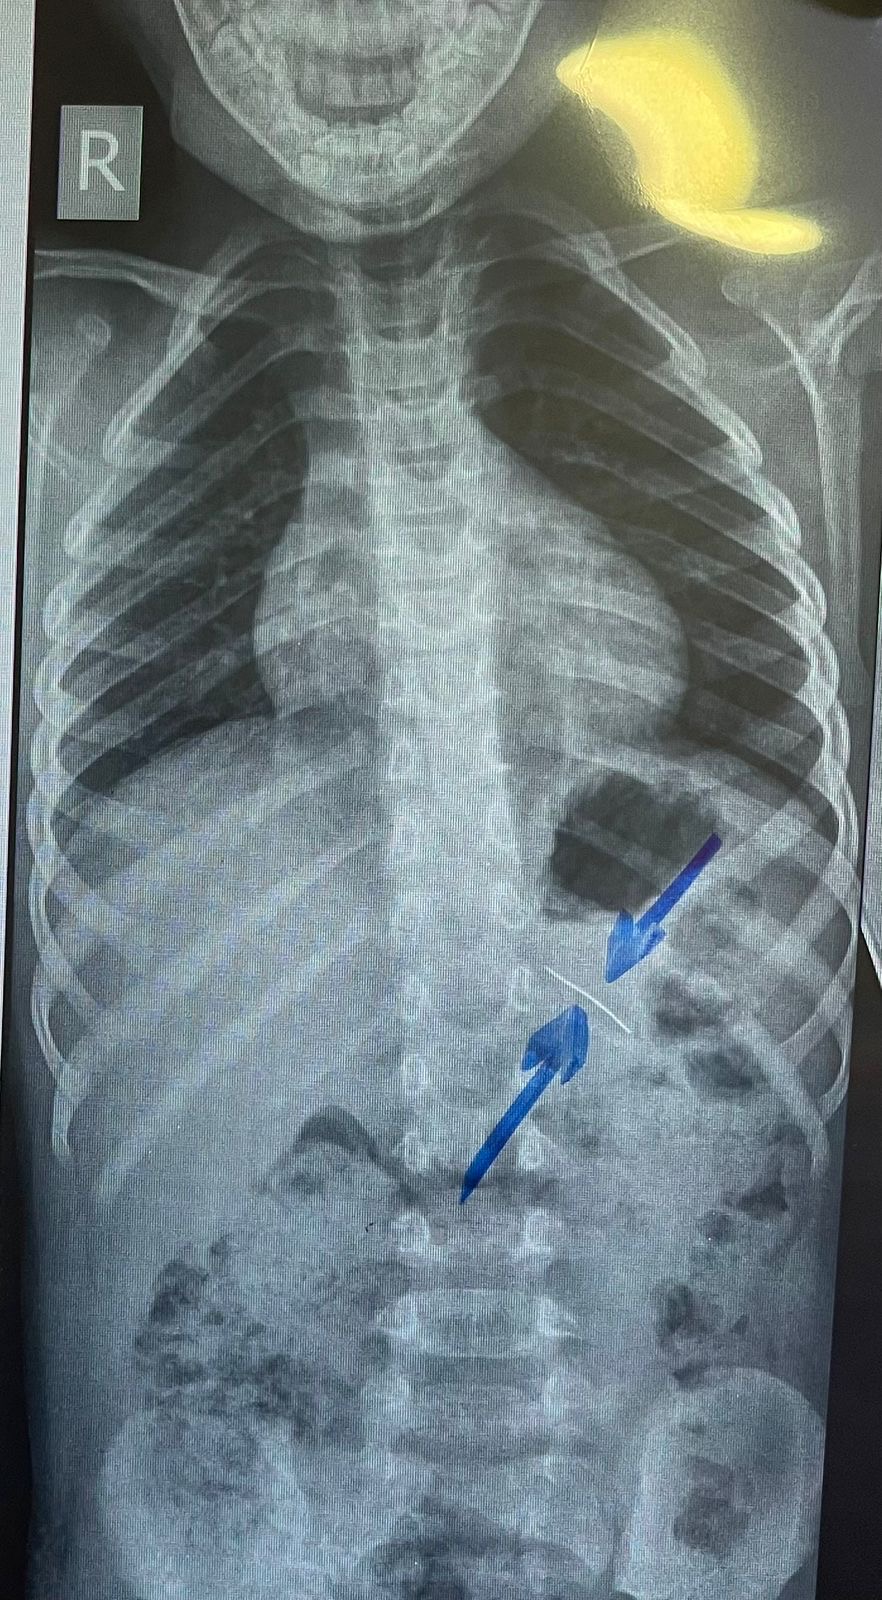

نجح فريق طبي من وحدة أمراض الجهاز الهضمي والكبد ومناظير الأطفال بقسم طب الأطفال بمستشفى جامعة سوهاج، في إجراء تدخل دقيق لاستخراج دبوس من معدة طفل يبلغ من العمر أربع سنوات، بإستخدام منظار معدة خاص بالأطفال، دون حدوث أي مضاعفات، وقد غادر الطفل المستشفى بعد ثلاث ساعات فقط من الإجراء، وهو في حالة صحية جيدة.

وأكد الدكتور أحمد كمال، المدير التنفيذي للمستشفيات الجامعية جامعة سوهاج، أن التعامل مع الحالة تم بسرعة وكفاءة، حيث تمكن الفريق الطبي من استخدام المنظار الخاص بالأطفال لاستخراج الدبوس دون أي تدخل جراحي، مما ساهم في خروج الطفل من المستشفى في نفس اليوم بحالة ممتازة.